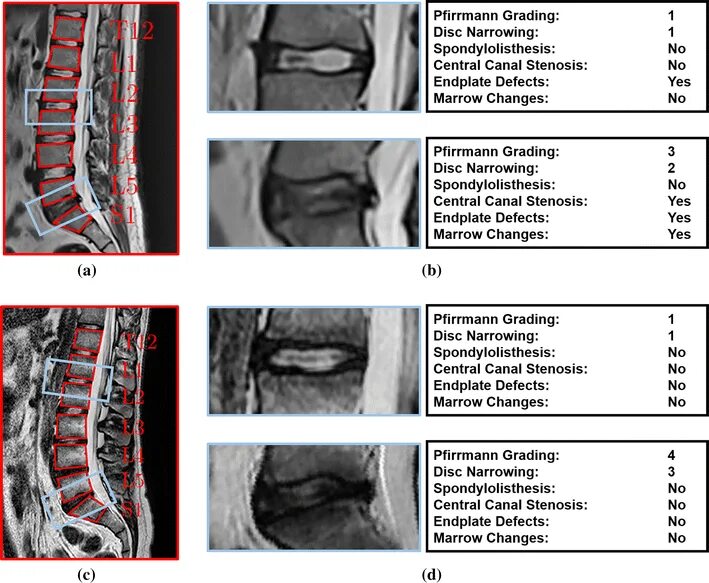

Дегенерация межпозвонкового диска по pfirrmann